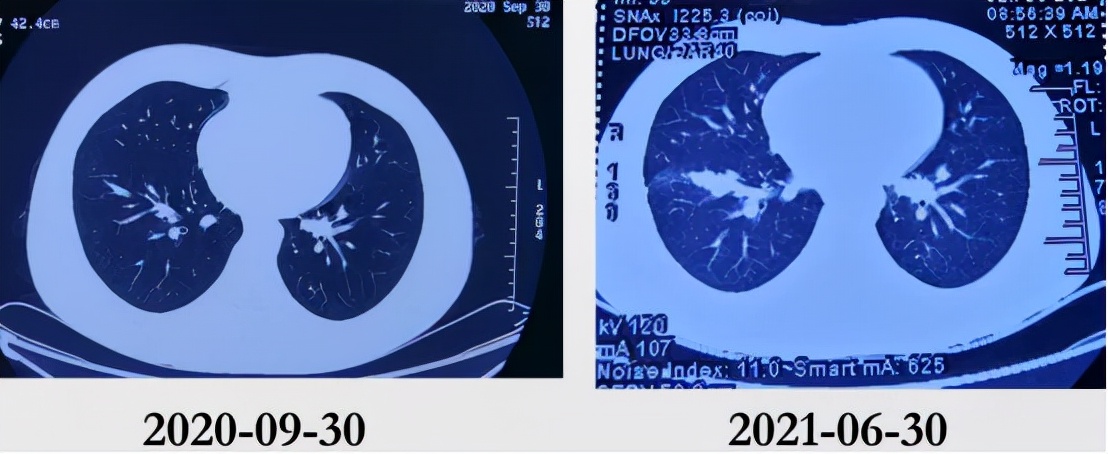

就诊于外地某三甲医院,行胸部CT(2020-09-30)检查提示右肺下叶前基底段少许小气道炎症,予「头孢克肟」治疗1个月,症状无明显好转,未进一步诊治。

入院前1月余(2021-6)患者出现活动后胸痛再发,部位为前胸,呈烧灼样疼痛,NRS 7分,向右侧上肢及左侧下肢放射,无压痛,以活动后和情绪激动后为著,持续3min后自行缓解。外院行运动平板试验阴性、超声心动图正常,胸部增强CT(2021-06-30)示右肺下叶前基底段实变影伴多发结节,轻度强化,纵隔及双侧腋下未见肿大淋巴结。后胸痛逐渐加重,多于变换体位后出现,持续5min后可自行缓解,伴胸闷、咳嗽,咳少量白痰,无咯血、盗汗,无乏力、消瘦。于外地某三甲医院住院,行PPD试验强阳性,血沉、肿瘤标志物、心脏CT、腹部超声、动态心电图未见异常。气管镜检查示左右主支气管及其各叶段支气管开口通畅,粘膜充血、水肿,可见少许脓性分泌物附着,诊断支气管粘膜慢性炎症,BALF抗酸染色、细菌、真菌培养阴性, mNGS NTM-DNA 35.59拷贝,MTB阴性,病理未见癌细胞;复查胸部CT示右肺中叶片状磨玻璃影,右肺门增大,右肺门向外支气管血管束增粗,右下肺基底段可见结节影,7区肿大淋巴结。外院住院期间体温波动于36.6-37.4℃,予左氧氟沙星静点、乙酰半胱氨酸雾化吸入治疗,症状无明显好转。患者自发病来,精神可,体力差,食欲可,睡眠差,二便正常,体重无明显变化。

外院CT(2020-09-30):

外院CT:

我们总结病例特点: 青年男性,慢性病程。既往体健进行性加重的胸痛,多与体位相关,活动加重,休息可缓解。呼吸道症状轻微,病程后期有低热,无其他系统性症状胸部CT提示右肺下叶轻度强化的阴影,及右肺门多发结节,沿支气管血管束分布,轻度强化,7区肿大淋巴结,无胸腔积液气管镜提示粘膜慢性炎症改变,BALF mNGS提示NTM可疑阳性。

陈起航主任 为我们深入解读了患者的胸部CT:

患者为年轻男性,病变为局灶性,位于右肺下叶基底段,为不规则的片状实变影,远端有小叶中心性分布的小结节,支气管近端可疑狭窄;纵膈窗提示右侧肺门淋巴结肿大。结合患者的年龄、呼吸道症状和肺内影像学特点,肺内病变应该首先应鉴别感染性病变,比如结核,当然并不是结核的好发部位,但结核的胸部影像学的表现很多,当然其他可疑的鉴别诊断很多,但是从发病率而言,我们不会首先考虑肿瘤。